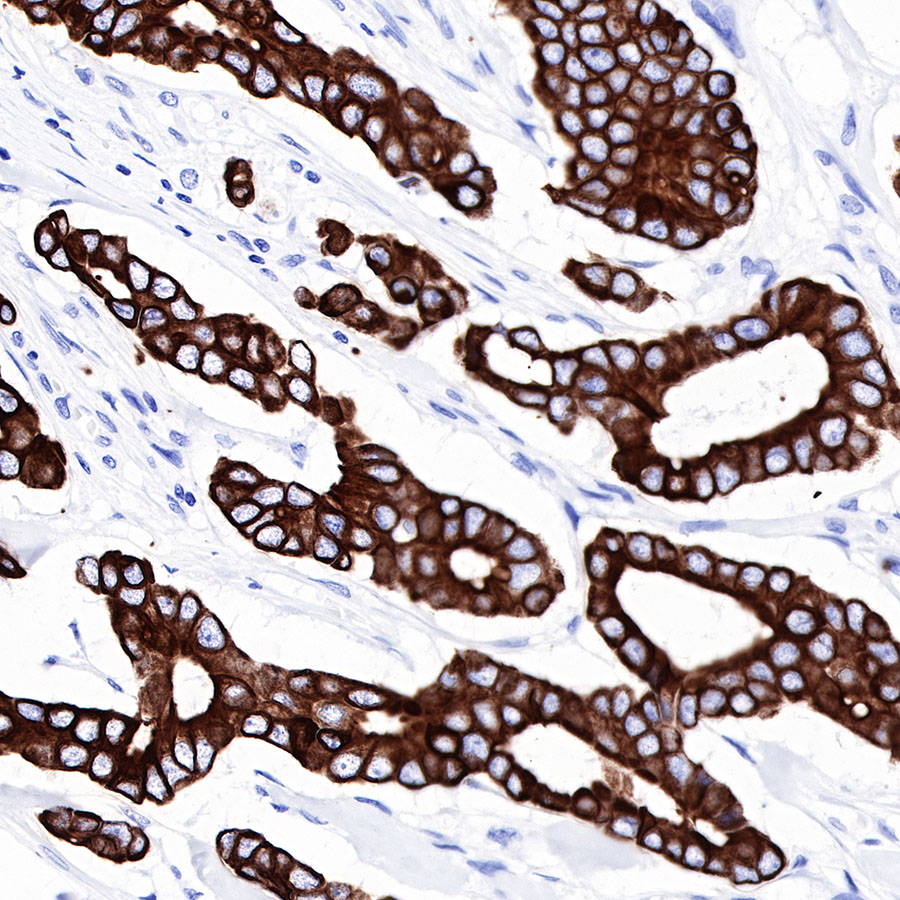

| IHC-P |

1:500-1:2000 |

Background

CK-LMW is low molecular weight cytokeratins and is expressed in monolayer or glandular epithelium of normal or tumor tissues, such as thyroid, breast, gastrointestinal or respiratory epithelium. It is expressed in adenocarcinoma and the vast majority of nonkeratinizing squamous cell carcinoma, but not in keratinizing squamous cell carcinoma. It combined with CK5/6 for diagnosis of adenocarcinoma and squamous carcinoma.